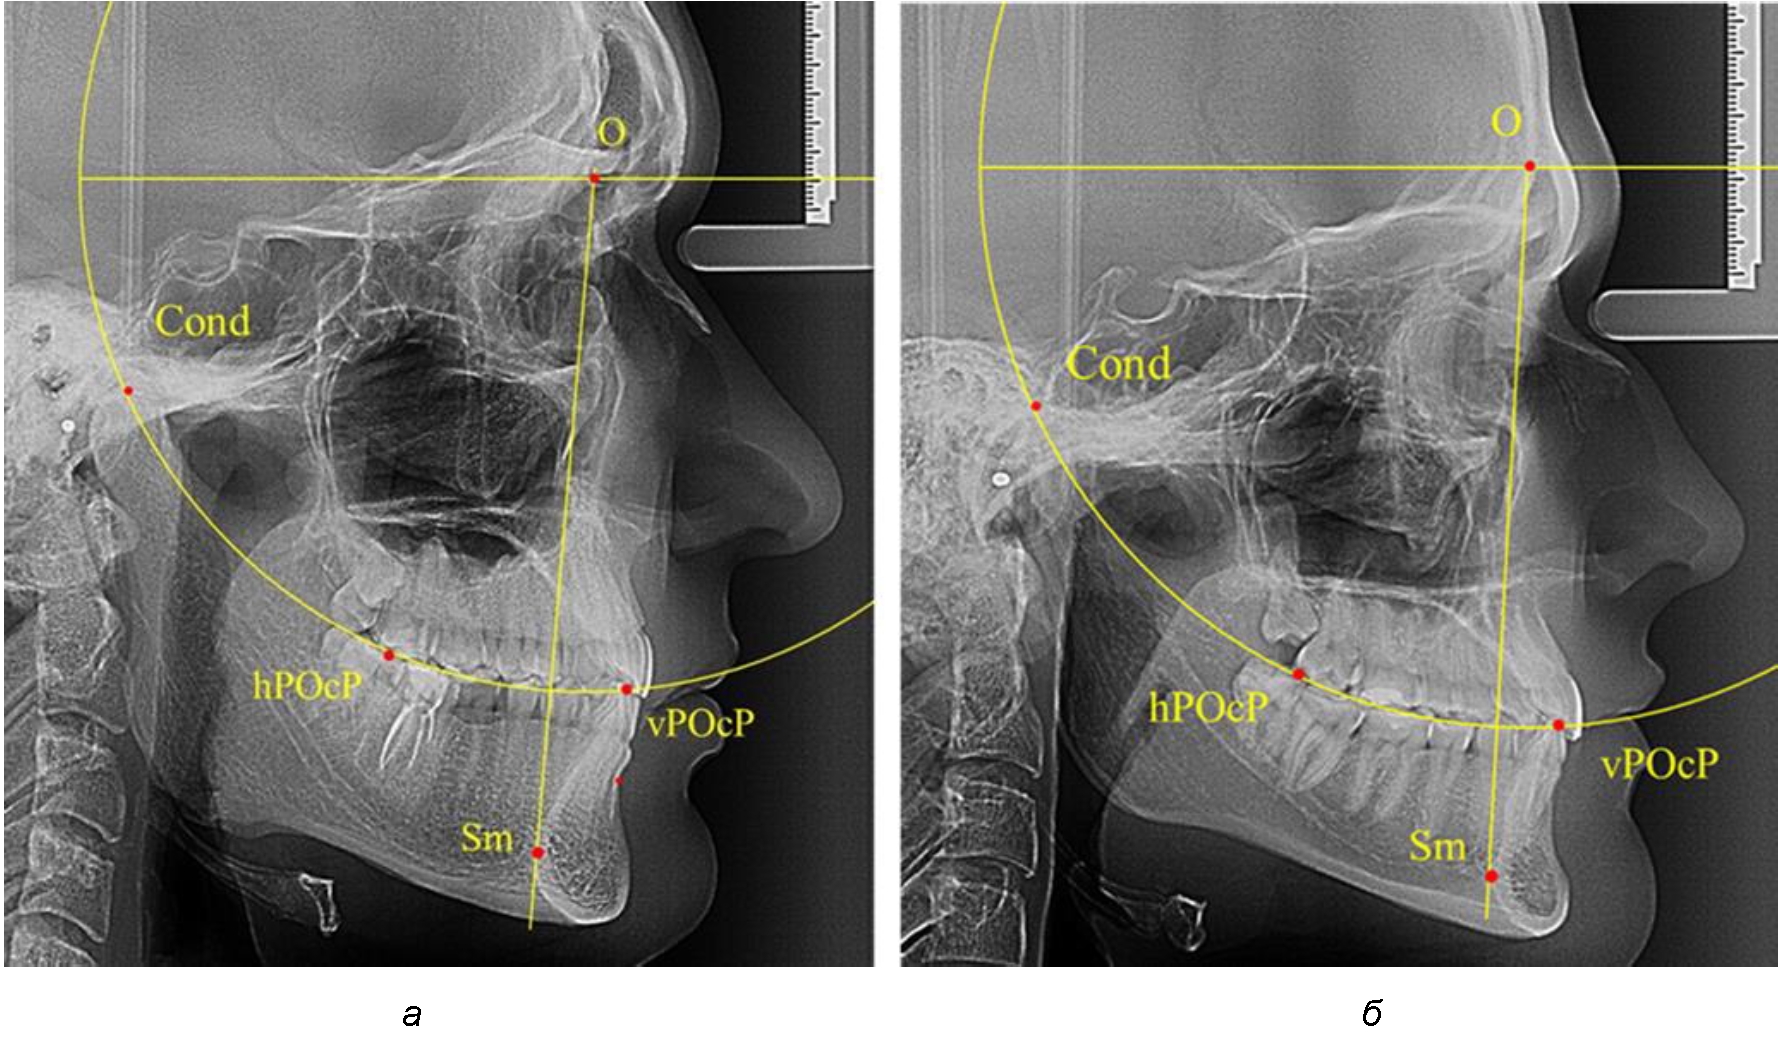

В группе рентгенограмм, выделенных по признаку протрузионного положения резцов, также проводилось распределение на подгруппы с учетом широтных размеров подбородочного выступа.

Анализ результатов показал, что практически при всех вариантах подбородочного выступа в данной группе исследования первые премоляры, как правило, располагались впереди стресс-оси Bimler. Рентгенограммы пациентов с протрузионным положением резцов при среднем и узком варианте подбородочного выступа представлены на рис. 3.

Таким образом, для людей с протрузионным типом зубочелюстных дуг характерно расположение первых премоляров впереди стресс-оси, и этот показатель не может быть использован в качестве выбора метода лечения аномалий для данной группы исследования вне зависимости от формы подбородочного выступа.

Рис. 3. Положение первых верхних премоляров при протрузии со средними (а) и узкими (б) размерами подбородка